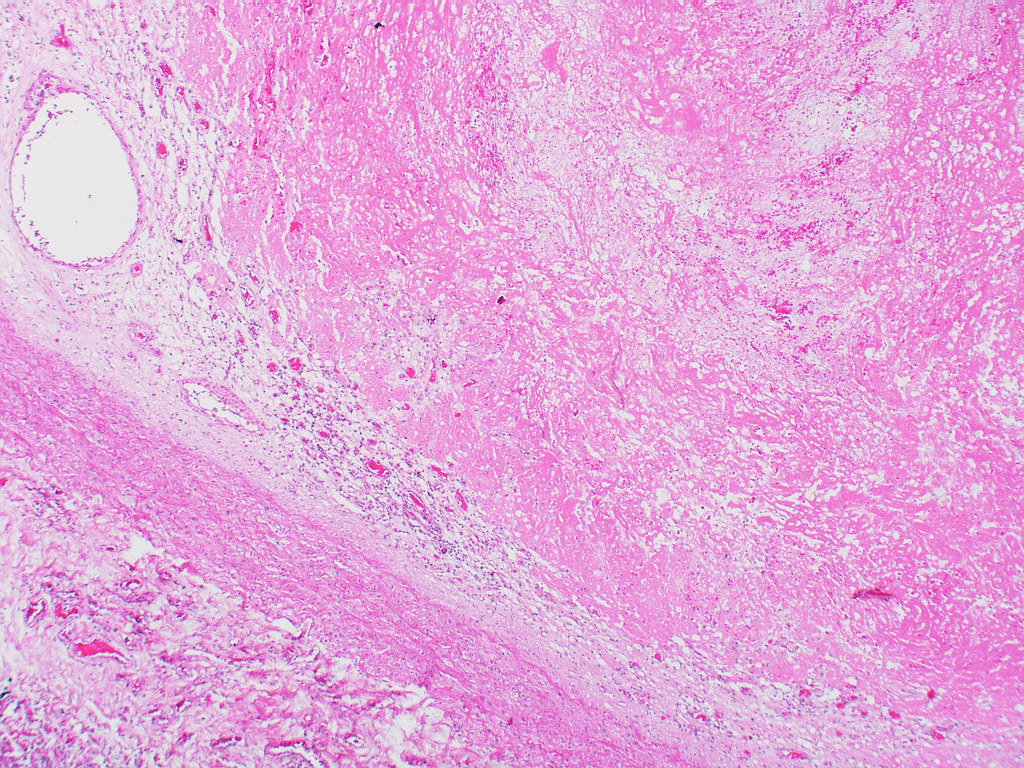

Thrombi in the arteries are usually pale in appearance as they consist mainly of platelets and fibrin that adhere to the arterial wall. Red cells are not trapped in the thrombi as they are swept away by the fast moving flow of blood.

In a large thrombus, alternating layers of platelets and red cells may be seen, which is termed as lines of Zahn.

Venous thrombi are usually friable and appear red in colour due to the numerous red cells that get trapped in the forming thrombi.